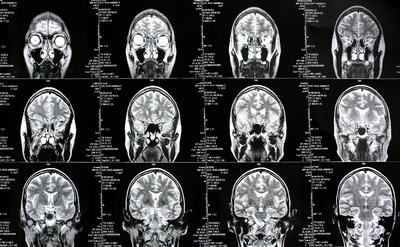

Sie sind hier: Startseite Nachrichten Gesundheit Bayern und Brandenburg senken Preise für Kontrastmittel deutlich ab Bild: Rike / pixelio.de